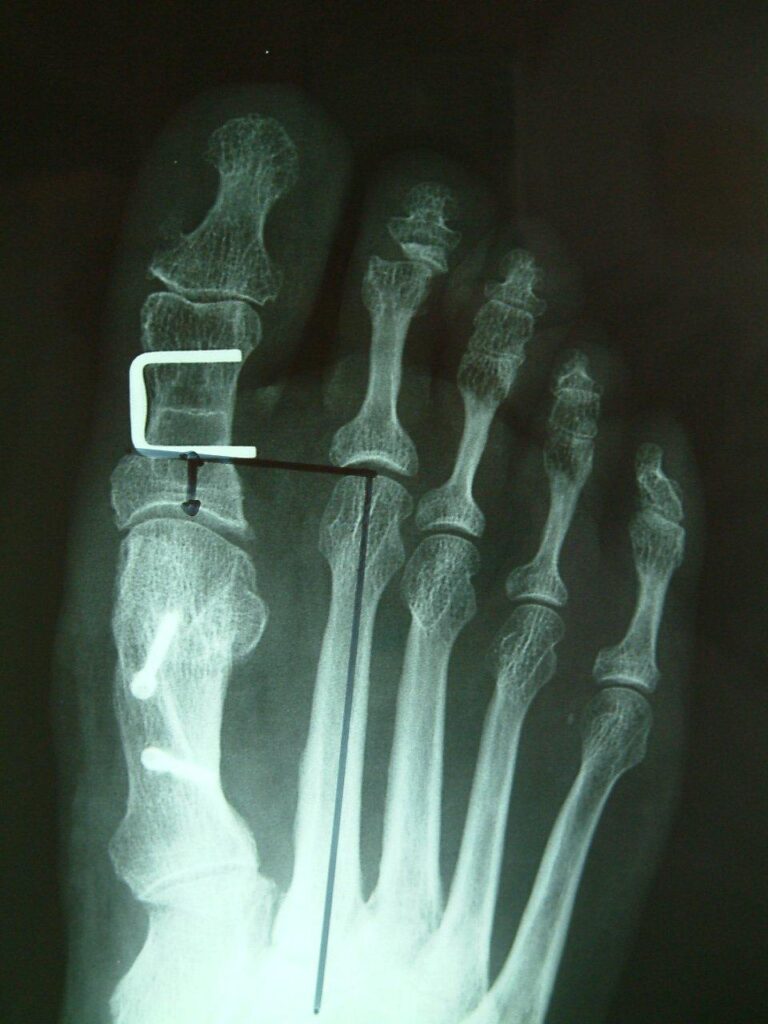

The common operative treatments of bunions involve bony correction through cuts of bone and fixation with screws as well as release of tight tissue structures and tightening of loose ones. Many operations for bunions have been tried over the years with varying levels of success. Techniques often vary from patient to patient depending or anatomy and bony alignment as well as soft tissue laxity.

The metalwork usually does not need to be removed. Recovery times and swelling vary from patient to patient.